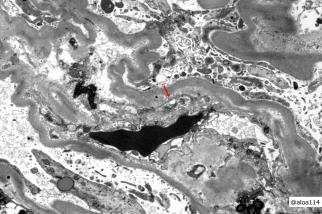

With the rapid development of self-supervised learning (e.g., contrastive learning), the importance of having large-scale images (even without annotations) for training a more generalizable AI model has been widely recognized in medical image analysis. However, collecting large-scale task-specific unannotated data at scale can be challenging for individual labs. Existing online resources, such as digital books, publications, and search engines, provide a new resource for obtaining large-scale images. However, published images in healthcare (e.g., radiology and pathology) consist of a considerable amount of compound figures with subplots. In order to extract and separate compound figures into usable individual images for downstream learning, we propose a simple compound figure separation (SimCFS) framework without using the traditionally required detection bounding box annotations, with a new loss function and a hard case simulation. Our technical contribution is four-fold: (1) we introduce a simulation-based training framework that minimizes the need for resource extensive bounding box annotations; (2) we propose a new side loss that is optimized for compound figure separation; (3) we propose an intra-class image augmentation method to simulate hard cases; and (4) to the best of our knowledge, this is the first study that evaluates the efficacy of leveraging self-supervised learning with compound image separation. From the results, the proposed SimCFS achieved state-of-the-art performance on the ImageCLEF 2016 Compound Figure Separation Database. The pretrained self-supervised learning model using large-scale mined figures improved the accuracy of downstream image classification tasks with a contrastive learning algorithm. The source code of SimCFS is made publicly available at https://github.com/hrlblab/ImageSeperation.